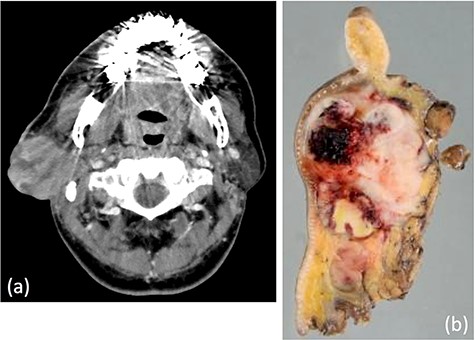

A 62-year-old man presented to our hospital after detecting a mass in the right parotid gland. He had no personal or family history of malignancy. On physical examination the mass was 5.0 × 5.0 cm in size with poor mobility. Computed tomography revealed a tumor (5.1 × 5.0 cm) within the right parotid gland that was enhanced by contrast (Fig. 1a). The tumor had an irregular shape with calcifications, a low-density area and the boundary between the tumor and surrounding tissues was indistinct. A malignant tumor of the right parotid gland was suspected, thus tumor resection with lymph node dissection was performed. The cut surface of the tumor was yellow–white with hemorrhage and necrosis (Fig. 1b). The tumor boundaries were ill-defined. The proliferation of three morphologically-different tumor cells was demonstrated on histopathologic examination. First, the cell type was atypical with abundant granular eosinophilic cytoplasm, large nuclei with coarse chromatin and prominent nucleoli. The cells were proliferative and invasive with duct-like, glandular and solid patterns (Fig. 2a and b). Frequent mitotic activity and necrosis were evident. The cells had the characteristics of a salivary duct carcinoma (SDC). Second, the atypical spindle-to-epithelioid cells with a clear cytoplasm were proliferative and invasive with trabecular, tubular and solid patterns (Fig. 2c and d). The stroma was hyalinized. The cells had the characteristics of a myoepithelial carcinoma (MC). Third, atypical duct-like structures were composed of two distinct cell layers. The inner layer was comprised of cuboidal cells with eosinophilic cytoplasm and round enlarged nuclei and the outer layer consisted of cells with clear cytoplasm and oval nuclei (Fig. 2e and f). The cells had the characteristics of an epithelial-myoepithelial carcinoma (EMC). In addition, the shape of the inner layer cell nuclei was similar to SDC. These three tumor types invaded the surrounding tissues and appeared to be a mixture of cells with reciprocal transfer in the same area (Fig. 3). Immunohistochemistry was performed using the Dako Envision+ System with dextran polymers conjugated to horseradish peroxidase (Dako, Glostrup, Denmark). The following primary antibodies (all purchased from Dako) were used: AR (AR441); αSMA (1A4); cytokeratin (AE1/AE3); EMA (E29); GCDFP-15 (23A3); polyclonal HER2; Ki-67 (MIB-1); p53 (DO7); p63 (DAK-p63); polyclonal S-100 and WT1 (6F-H2). The results of immunochemistry staining are shown in Table 1. Briefly, most of the SDC cells were positive for cytokeratin AE1/AE3, EMA, AR (Fig. 4a), HER2 (Fig. 4b) and p53. In contrast, most of the MC cells were positive for p63 (Fig. 4c), αSMA, S-100 (Fig. 4d) and WT-1, and weakly positive for cytokeratin AE1/AE3. Most of the EMC inner layer cells were positive for cytokeratin AE1/AE3 (Fig. 5a), EMA, and p53, and weakly positive for AR and HER2 (Fig. 5b). Most of the EMC outer layer cells were positive for p63, αSMA, S-100 and WT-1, and weakly positive for cytokeratin AE1/AE3 (Fig. 5a). In the mixed cell area, most of the EMC inner layer cells were positive for cytokeratin AE1/AE3, most of the EMC outer layer cells and MC cells were weakly positive for CK AE1/AE3 (Fig. 5c), and most of the EMC outer layer cells and MC cells were positive for p63 (Fig. 5d).

(a) Computed tomography revealed a tumor, 5.1 × 5.0 cm in size, within the right parotid gland enhanced by contrast. The tumor had an irregular shape with calcifications, low-density area and the boundary between the tumor and surrounding tissues was indistinct. (b) Macroscopically, the cut surface of the tumor was yellow–white with hemorrhage and necrosis. The tumor boundary was ill-defined.